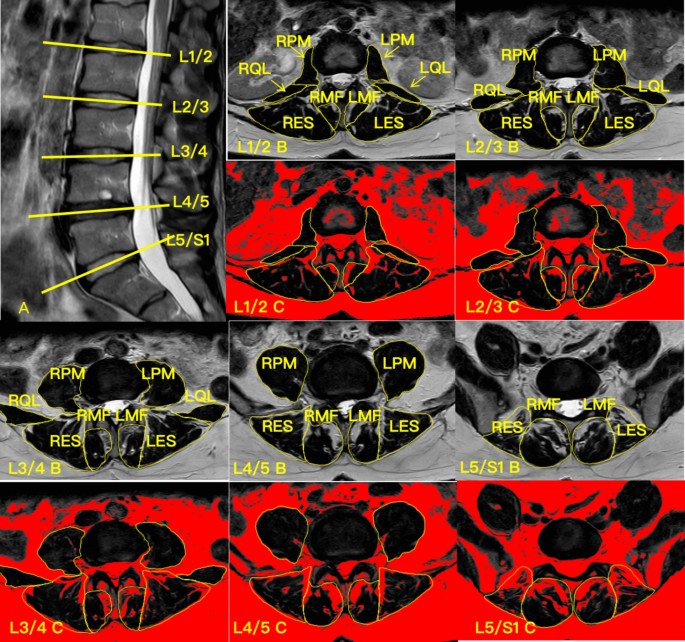

The cross-sectional area (CSA) and functional cross-sectional area (FCSA) of the PM, QL, MF, and ES were assessed at the mid-disc level of all lumbar spinal segments (Fig. 1). Due to measurement limitations, the PM muscles were evaluated from L1/2 to L5/S1 and the QL from L1/2 to L3/4. FI was calculated using the formula FI = ((CSA − FCSA)/CSA)*100. Three key indices were used to assess paraspinal muscle asymmetry: the CSA asymmetry Index (CAI), FCSA asymmetry Index (FCAI), and FI asymmetry Index (FIAI). These indices quantify the asymmetry between the left and right sides of the muscles:

MRI of a subject’s lumbar spine and target muscle measurements. (A) Sagittal view of the lumbar spine, with the yellow line indicating the location of the measured cross-sectional MRI; (B) Cross-sectional area of the psoas major (PM), quadratus lumborum (QL), multifidus (MF), and erector spinae (ES) at the L1/2 segment; (C) Functional cross-sectional area of the PM, QL, MF and ES at the L1/2 segment. LPM left psoas major, LQL left quadratus lumborum, LMF left multifidus, LES left erector spinae, RPM right psoas major, RQL right quadratus lumborum, RMF right multifidus, RES right erector spinae.